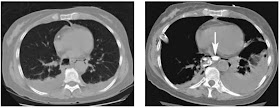

A 62 years oled male presented with severe chest pain and hypotension after vomiting.

Ct shows bilateral pleural effusion and pneumomediastinum to the aorta and to the right of the oesophagus. Subsequent CT with oral contrast shows dense contrast in the oesophagus (arrow) and leakage into the irregular complex right mediastinal collection.

The diagnosis is Boerhaave syndrome.

Spontaneous rupture of the oesophagus during vomiting.